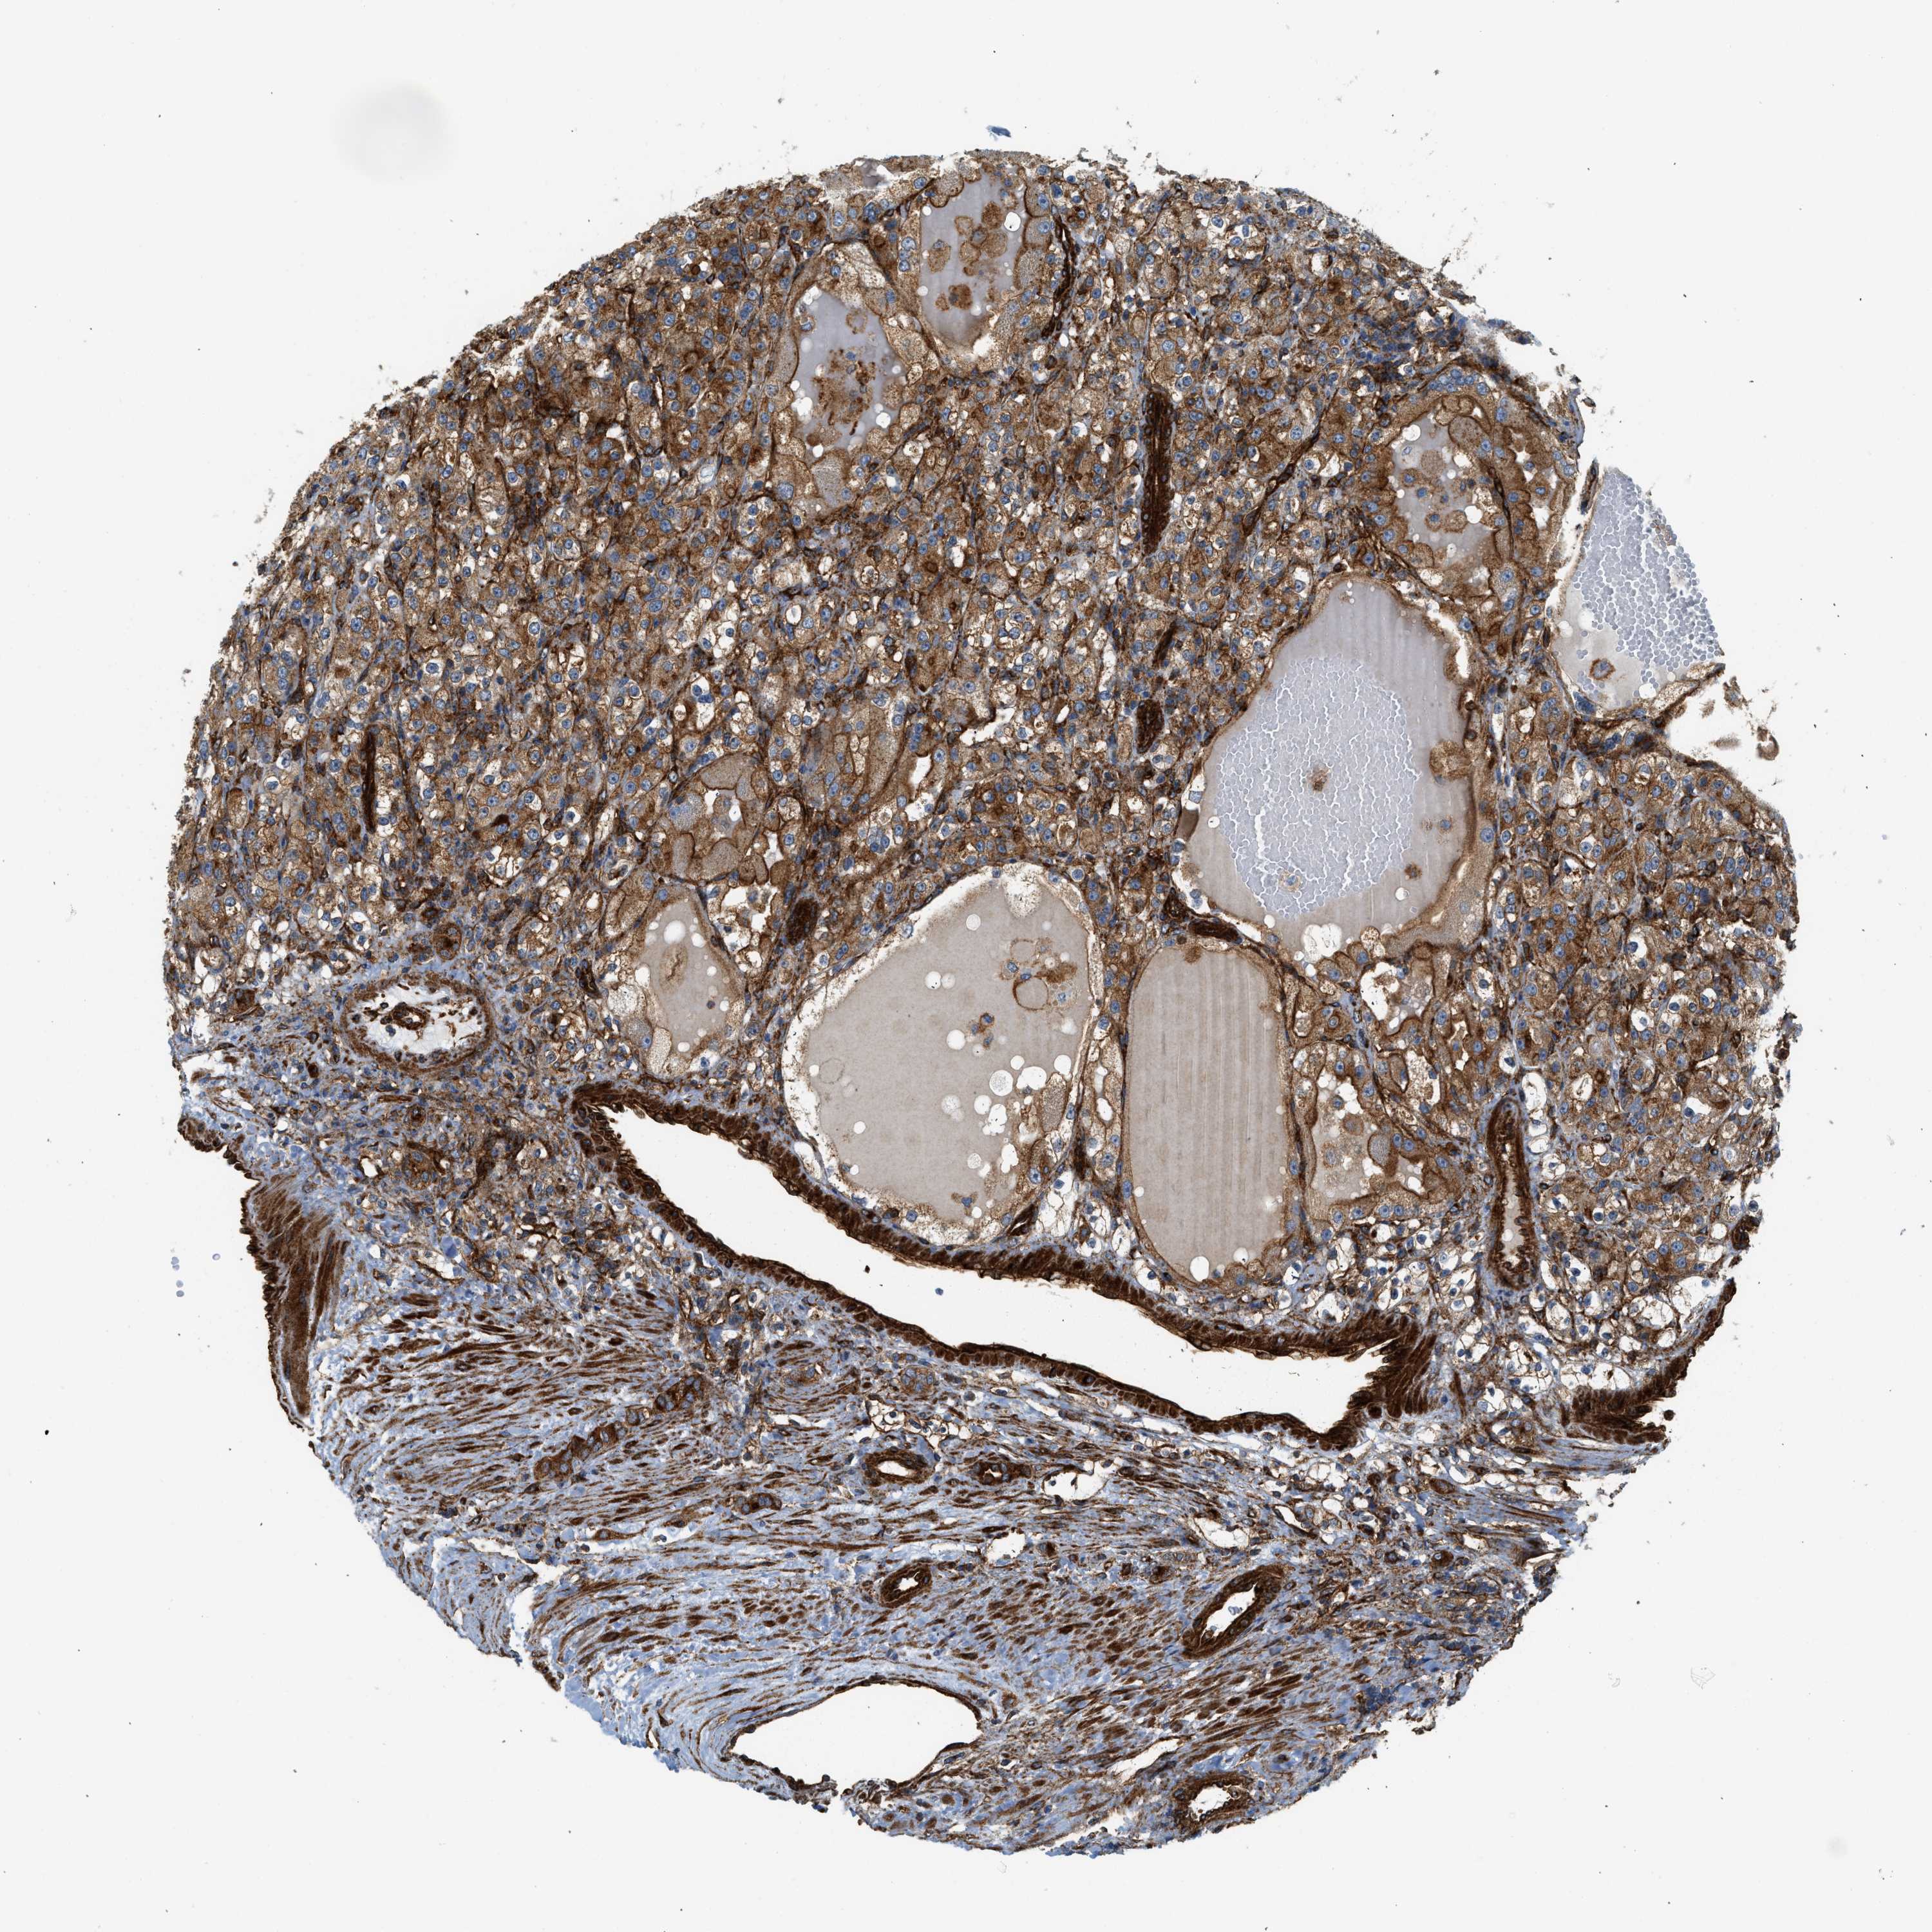

KIDNEY RENAL CLEAR CELL CARCINOMA (VALIDATION) - Interactive survival scatter ploti

The Survival Scatter plot shows the clinical status (i.e. dead or alive) for all individuals in the patient cohort, based on the same data that underlies the corresponding Kaplan-Meier plots. Patients that are alive at last time for follow-up are shown in blue and patients who have died during the study are shown in red.

The x-axis shows the expression levels (FPKM) of the investigated gene in the tumor tissue at the time of diagnosis. The y-axis shows the follow-up time after diagnosis (years). Both axes are complimented with kernel density curves demonstrating the data density over the axes. The top density plot shows the expression levels (FPKM) distribution among dead (red) and alive patients (blue). The right density plot shows the data density of the survived years of dead patients with high and low expression levels respectively, stratified using the cutoff indicated by the vertical dashed line through the Survival Scatter plot. This cutoff is automatically defined based on the FPKM cutoff that minimizes the p-score. The cutoff can be changed by dragging the vertical line or by entering a cutoff value in the square labeled "Current cut-off".

Under the Survival Scatter plot the p-score landscape (black curve; left axis) is shown together with dead median separation (red curve; right axis). Dead median separation is the difference in median mRNA expression between patients who have died with high and low expression, respectively. It is calculated as follows: median FPKM expression of dead patients with high expression - median FPKM expression of dead patients with low expression. This is intended to aid the user in visually exploring custom cutoffs and the associated p-scores and dead median separation.

Individual patient data is displayed and can be filtered by clicking on one or more of the category buttons on the top of the page. Categories describing expression level and patient information include: high, low, alive, dead, female, male and tumor stages. The scale of the x-axis can be toggled between linear and log-scale by clicking on the "x log" button. Mouse-over function shows TCGA ID, patient information and mRNA expression (FPKM) for each patient.

& Survival analysisi

Kaplan-Meier plots summarize results from analysis of correlation between mRNA expression level and patient survival. Patients were divided based on level of expression into one of the two groups "low" (under cut off) or "high" (over cut off). X-axis shows time for survival (years) and y-axis shows the probability of survival, where 1.0 corresponds to 100 percent.

HIP1 is validated prognostic, high expression is favorable in Kidney Renal Clear Cell Carcinoma (validation)

Best expression cut offi

Based on the FPKM value of each gene, patients were classified into two groups and association between prognosis (survival) and gene expression (FPKM) was examined. The best expression cut-off refers the FPKM value that yields maximal difference with regard to survival between the two groups at the lowest log-rank P-value. Best expression cut-off was selected based on survival analysis .

When clicking on this number, the vertical dashed line indicating cut-off, the interactive survival plot, and the Kaplan-Meier curve will be adjusted to show results based on the best expression cut-off.

: 19.11

TCGA RNA samplesi

RNA-seq data is reported as average FPKM (number Fragments Per Kilobase of exon per Million reads), generated by the The Cancer Genome Atlas (TCGA) .

Normal distribution across the dataset is visualized with box plots, shown as median and 25th and 75th percentiles. Points are displayed as outliers if they are above or below 1.5 times the interquartile range. FPKM values of the individual samples are presented next to the box plot.

Average pTPM 17.6

Number of samples 100